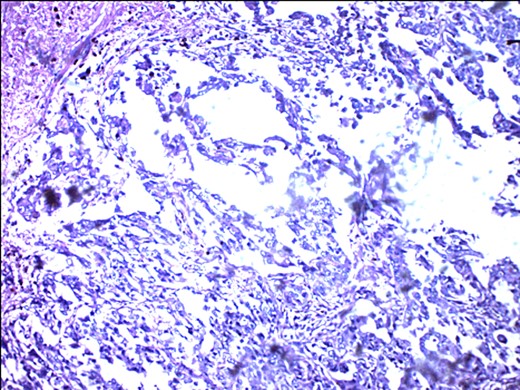

S-100 cytoplasmic positivity in keeping with melanocytic differentiation. Immunohistochemistry.

Tyrosinase positivity in keeping with melanocytic differentiation.